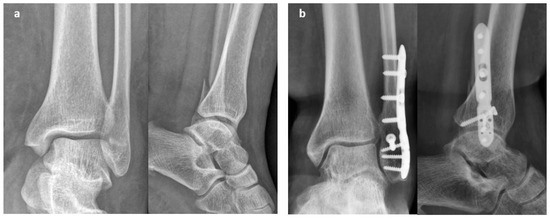

2.1. Surgical Procedure